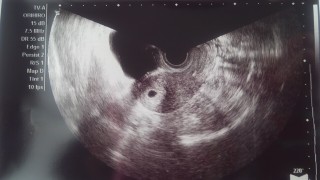

最終月経からしたら7w0dのはず! でも、生理不順で排卵ずれたりで、先生には5wぐらいの大きさ。 正常妊娠おめでとう!って言ってもらえました

次は2週間後にまた受診(^ω^)

心拍確認できますように!